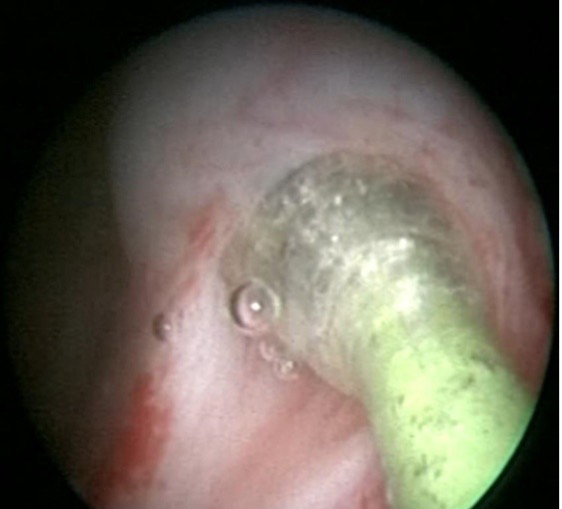

对于绝大多数输尿管狭窄,经尿道输尿管镜下高压球囊扩张术是首选的微创治疗方法。该技术无手术切口,对长度<75px的输尿管狭窄效果尤佳。本院采用质量最佳的进口的BARD输尿管扩张球囊导管(医保覆盖),扩张压力为同类最大,可达30个大气压,扩张成功率高。